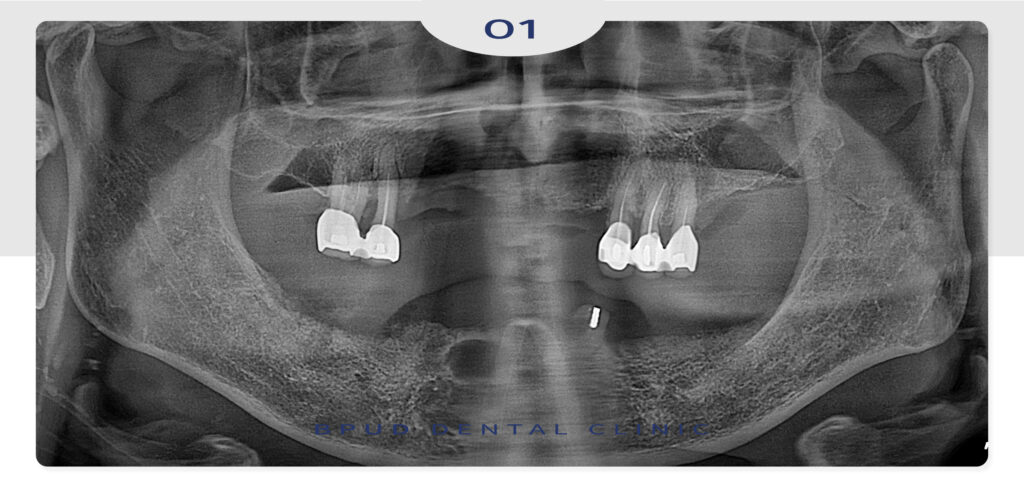

오늘은 부분 틀니의 사용이 많이 불편하셨던

환자분께서 전체 임플란트 식립을 진행하신

환자분을 소개해 드리도록 하겠습니다.

환자분께서는 틀니를 사용하신 지

5년 정도 되었는데 잇몸이 너무 불편하고

아프셔서 약국에서 진통제를 구입하여

드시면서 버티고 있는 중이라고 말씀해 주셨는데요.

부평임플란트 상담을 위해 지인 분의 소개로

내원해 주셨다고 합니다.

남아 있는 치아들은 부분 틀니의 지대치로

사용하고 있으나 동요도가 있고 우식이 심하여

더 이상 살려쓰시기에는 어려움이 있을 것이라

판단되어 잔존 치아를 모두 발치한 후

전체 임플란트 식립을 진행하였는데요.